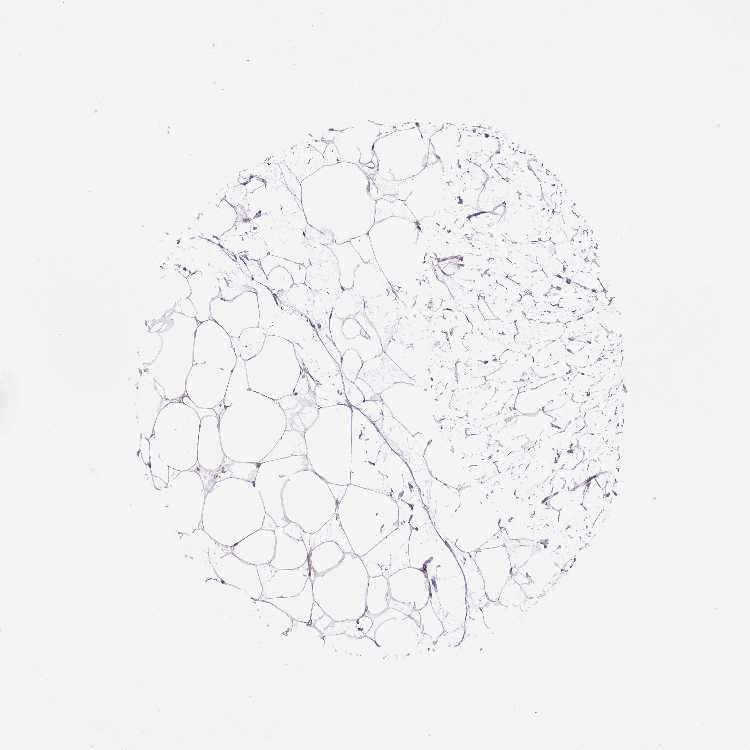

TISSUE PRIMARY DATA BREAST Show tissue menu

BREAST - Antibody stainingi

Antibody staining in the annotated cell types in the current human tissue is reported as not detected, low, medium, or high, based on conventional immunohistochemistry profiling in selected tissues. This score is based on the combination of the staining intensity and fraction of stained cells.

Each image is clickable and will lead to virtual microscopy that enables deeper exploration of all samples and also displays staining intensity scores, fraction scores and subcellular localization as well as patient and tissue information for each sample.

Antibody HPA065505Antibody HPA067322

Adipocytes LowNot detected

Glandular cells Not detectedNot detected

Myoepithelial cells Not detectedNot detected